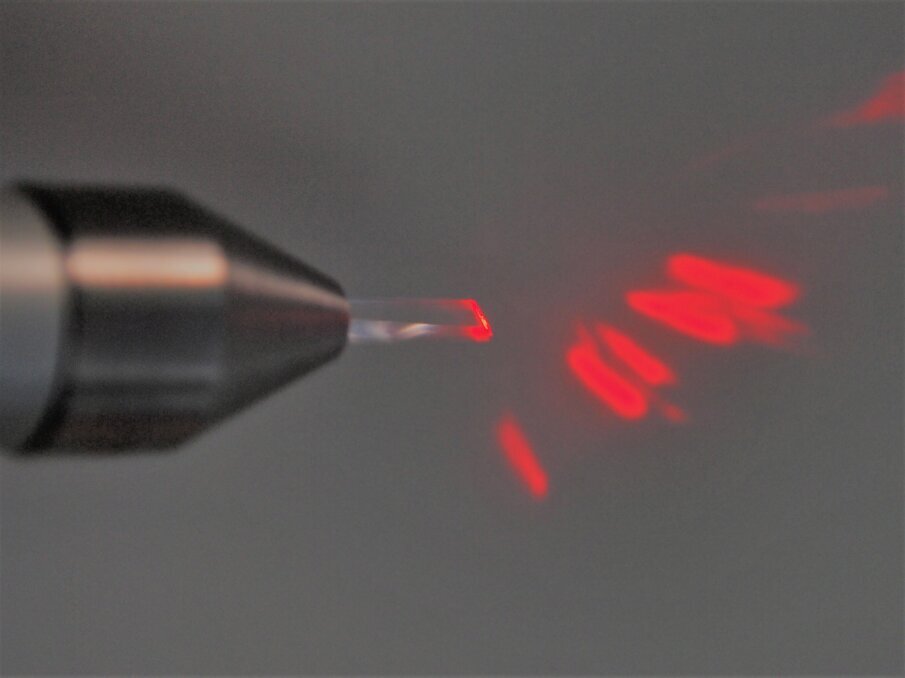

Fig. 1 - Inserto intercambiabile in zaffiro montato su specifico manipolo. In modalità non attivata è possibile osservare la proiezione del fascio guida attraverso il prisma in zaffiro.

Questi ultimi sono utilizzati per specifiche finalità a seconda della lunghezza d’onda e del loro mezzo attivo. I laser a diodi con emissione nel vicino infrarosso vengono applicati con successo da anni nella chirurgia dei tessuti molli orali ed extraorali2-4.

I laser a diodi Near InfraRed (NIR) da 915 nm possono essere considerati una scelta versatile per le applicazioni sui tessuti molli intra ed extra-orali oro-maxillofacciali: hanno come target specifici cromofori endogeni come melanina ed emoglobina e una affinità per l’acqua superiore rispetto ai laser da 808 nm9-12. Presentano inoltre unì affinità per l’emoglobina superiore rispetto a 980 nm ed incontrano inoltre uno dei picchi di assorbimento del tessuto adiposo 9-12.